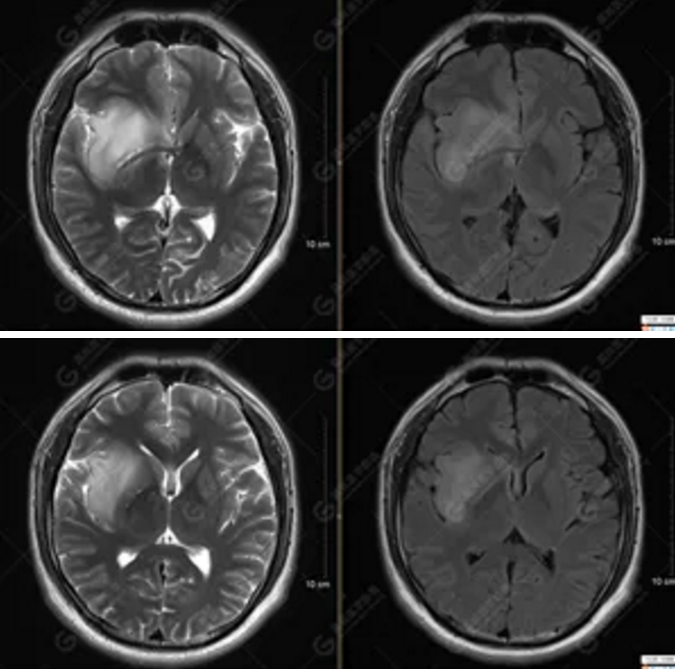

MR影像圖

【MRI平掃及增強(qiáng)檢查所見(jiàn)】右側(cè)額顳島葉、右側(cè)海馬及右側(cè)基底節(jié)區(qū)見(jiàn)一團(tuán)塊狀異常信號(hào)影,累及右側(cè)下丘腦及視交叉,大小約5.1cm×4.5cm×4.3cm,呈長(zhǎng)T1長(zhǎng)T2信號(hào),F(xiàn)LAIR序列呈等、稍高信號(hào),DWI序列呈稍高信號(hào),ADC圖高信號(hào),增強(qiáng)后無(wú)明顯強(qiáng)化;病灶周?chē)?jiàn)片狀長(zhǎng)T1長(zhǎng)T2水腫信號(hào)影,F(xiàn)LAIR序列呈高信號(hào),病灶內(nèi)見(jiàn)右側(cè)大腦中動(dòng)脈穿行。余腦實(shí)質(zhì)內(nèi)未見(jiàn)局灶性信號(hào)異常,增強(qiáng)后未見(jiàn)異常強(qiáng)化。右側(cè)側(cè)腦室輕度受壓,余腦室、腦池大小、形態(tài)均正常,中線(xiàn)結(jié)構(gòu)居中